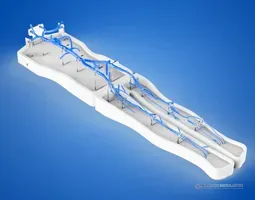

Radial Artery Puncture Operation Model (Ultrasound Guided) adalah simulator lengan bawah untuk pelatihan kanulasi arteri radialis dengan panduan USG. Arteri radialis dibuat berdasarkan data CT manusia.

Material komposit khusus memungkinkan visualisasi arteri yang jelas di layar USG *real-time*. Memberikan sensasi ‘tembus’ (*breakthrough*) yang realistis saat jarum menembus dinding arteri.

Drawing of Radial Artery Puncture Operation Model (Ultrasound-Guided)